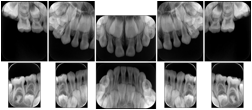

- OO-1. Intra-oral Full Mouth Series Structured Display